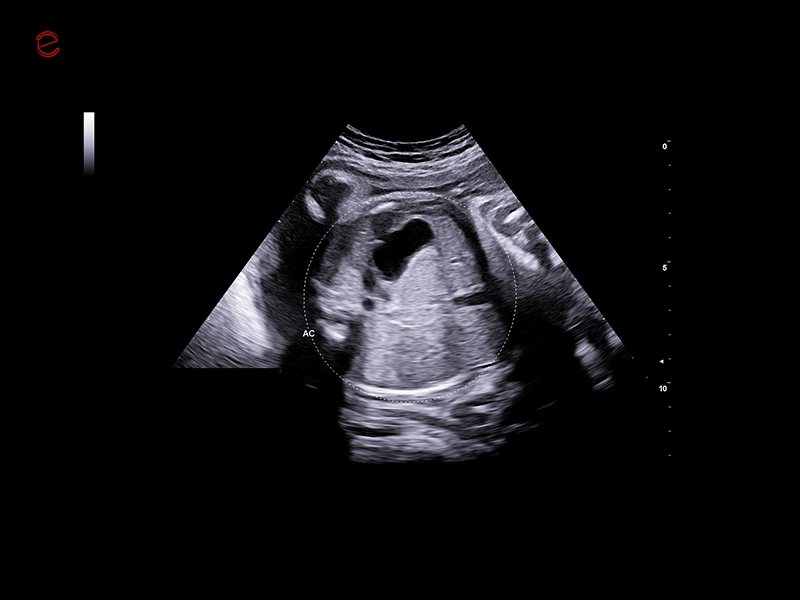

MyLab™C25 - AUTO OB

MyLab™C25 - AUTO OB